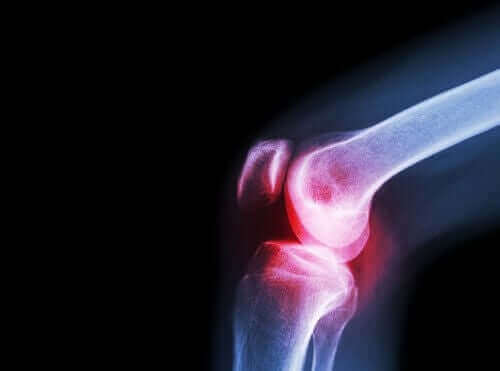

بالإضافة إلى ذلك، يتم وصفه لعلاج الألم والالتهاب المزمنين المرتبطين بالأمراض المزمنة كهشاشة العظام، التهاب المفاصل الروماتويدي، والتهاب الفقرات.

هو مرض مناعي ذاتي التهابي مزمن يصيب عدد من المفاصل ويؤدي إلى أعراض عامة غير محددة.

إذا لم يتم التعامل مع هذه الحالة بشكل صحيح، يمكن أن تؤدي إلى تقييد الحركة بشكل كبير، وهو ما يؤدي إلى تخفيض جودة حياة المريض بشكل كبير.

فيما يتعلق بالأعراض، تؤدي الحالة إلى ظهور ألم وتصلب، وصعوبة في تحريك المفاصل الكبيرة والصغيرة في مناطق مختلفة من الجسم.